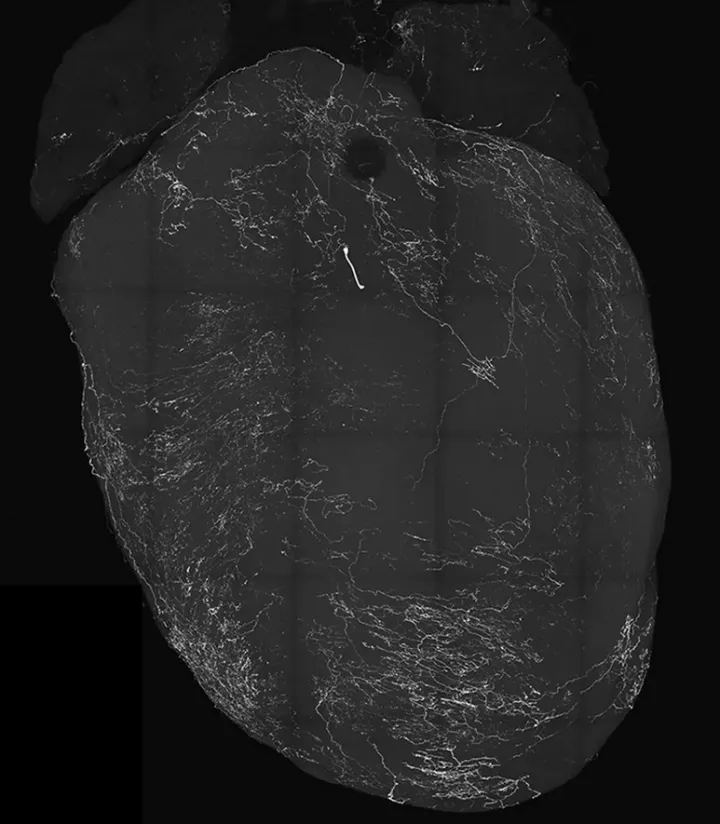

Сенсорные нейроны блуждающего нерва в сердце, которые вызывают обморок. Сенсорные нейроны блуждающего нерва в сердце, которые вызывают обморок.© Augustine Lab

Опираясь на это исследование, команда сосредоточилась на определённом типе нервных клеток под названием блуждающие сенсорные нейроны (VSN). Эксперименты показали, что VSN, которые экспрессируют особый белок NPY2R, играют ключевую роль в реакции на обморок. Когда учёные простимулировали эти нейроны у мышей при помощи оптогенетики, зверьки внезапно потеряли сознание.